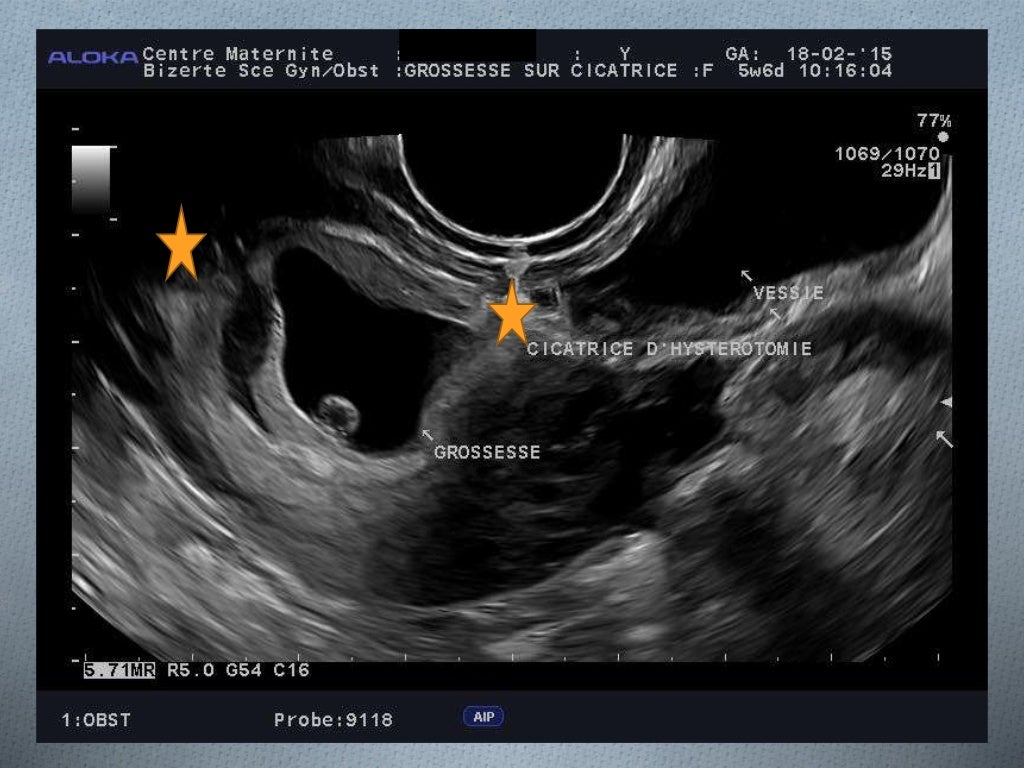

Césarienne cicatrice aspect échographique 3D omniview triangle ou goutte d'eau. Certaines femmes décrivent une douleur sourde et persistante au niveau de la cicatrice, une sensation de tension ou de tiraillements. La douleur post-césarienne lors d'une deuxième grossesse se manifeste de diverses manières, variant en intensité et en localisation